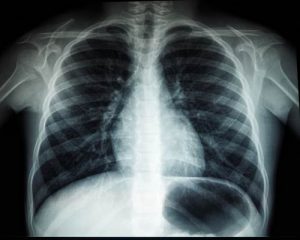

РентгенПервое назначение при подозрении на патологию дыхательных органов — рентгенография. Обследование проводят в 2-х проекциях: фас и профиль. Рентген-процедура помогает сделать правильные первые выводы о заболевании и провести дифференциальную диагностику — то есть исключить болезни со сходной симптоматикой.